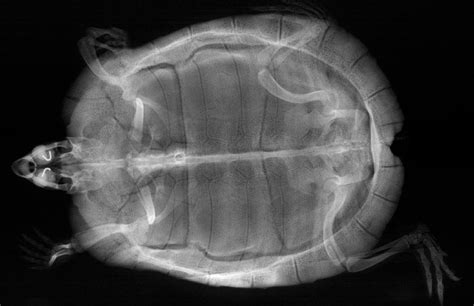

So, how exactly do we get to see those amazing inside views of our turtle pals? It’s all thanks to the incredible technology of turtle x-rays . Basically, x-rays use a special kind of radiation that can pass through soft tissues like skin and organs but gets absorbed more by denser materials like bone. When a turtle is placed in front of an x-ray machine, the radiation beams pass through its body. Different parts of the body absorb this radiation to varying degrees. The parts that absorb more radiation (like bones and dense foreign objects) block the x-rays, while softer tissues let more pass through. These differences in absorption are then captured on a special detector, creating a black-and-white image that shows us the internal structures. Think of it like a shadow puppet show, but for the inside of a turtle! It’s a pretty standard procedure in veterinary medicine for reptiles, and it’s crucial for diagnosing a range of issues, from internal injuries and infections to problems with their digestive system or reproductive organs. The quality of the image depends on several factors, including the turtle’s size, the x-ray machine’s power, and the positioning of the turtle. Vets often take multiple views, usually a lateral (side) view and a ventrodorsal (from top to bottom) view, to get a comprehensive understanding of the turtle’s anatomy and any abnormalities. It’s a bit like looking at a 3D object from different angles to really get a feel for its shape and structure. We often need to sedate or anesthetize the turtle to ensure it stays perfectly still during the scan, which is vital for obtaining clear, diagnostic-quality images. Any movement can blur the image, making it difficult to interpret. So, while it might seem simple, there’s a whole lot of science and care that goes into capturing those revealing turtle x-rays .

Reading the Bones: What Vets Look For in Turtle X-rays

Now, for the real nitty-gritty: what are vets actually looking for when they examine turtle x-rays ? It’s not just about spotting a weird shape; it’s a careful, detailed analysis. First off, they’re scrutinizing the skeletal structure . This includes the bones of the limbs, the spine, and critically, the carapace (top shell) and plastron (bottom shell). They’re checking for proper mineralization – are the bones dense and white, or are they looking a bit gray and translucent? This is a key indicator of metabolic bone disease. They’ll also look for any fractures or dislocations , whether from trauma or underlying weakness. The alignment of the bones is also super important; any unnatural angles or breaks in the continuity of the bone are red flags. Next up is the coelomic cavity . This is where the magic happens – vets can see the outlines of internal organs like the liver, kidneys, and heart, although their details aren’t always super clear on a standard x-ray. What they can often see are abnormalities. This includes foreign bodies – those pesky swallowed objects we talked about. They’ll appear as distinct, often dense shapes in the digestive tract. They also look for signs of organ enlargement or unusual masses , which could indicate tumors or other growths. In females, the presence and position of eggs are a major focus. They’ll count them, assess their size, and check if they are properly formed or if there are signs of resorption (where the body reabsorbs egg material, a serious complication). For respiratory issues , vets examine the lungs. While not always perfectly clear, signs like increased opacity (whiteness) in the lung fields can suggest fluid accumulation or pneumonia. Finally, they’ll assess the overall body condition . Are the bones looking healthy? Is there any evidence of organ displacement? It’s a holistic view, piecing together all the visual clues from the turtle x-rays to build a picture of the turtle’s health. It’s a bit like being a detective, using the x-ray image as the crime scene to uncover what’s really going on inside.